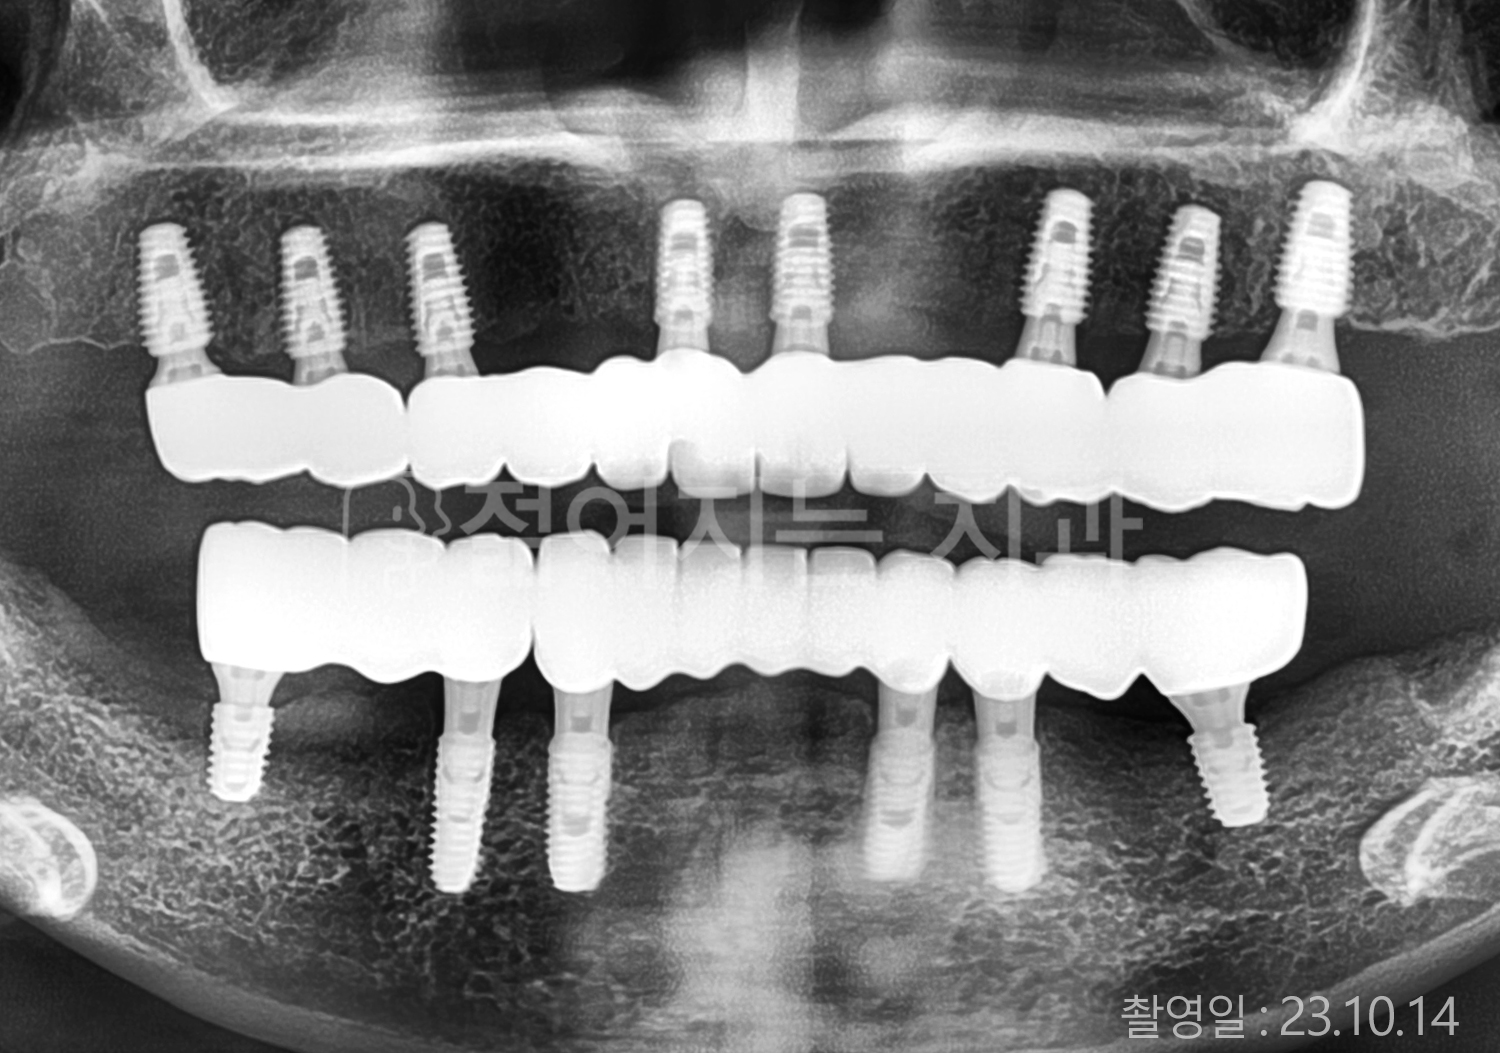

• 80대 전체치아 10개 이상 임플란트

• 60대 고혈압, 당뇨, 고지혈증 전체치아 10개 이상 임플란트

• 60대 전체치아 10개 이상 임플란트

• 60대 고혈압, 고지혈증 전체치아 10개 이상 임플란트

• 50대 고혈압, 당뇨, 고지혈증 전체치아 10개 이상 임플란트

• 70대 골다골증, 파킨스병 전체치아 10개 이상 임플란트

• 40대 전체치아 10개 이상 임플란트

• 60대 골다골증 전체치아 10개 이상 임플란트

• 40대 고혈압 전체치아 10개 이상 임플란트

• 50대 전체치아 10개 이상 임플란트

• 70대 전체치아 10개 이상 임플란트